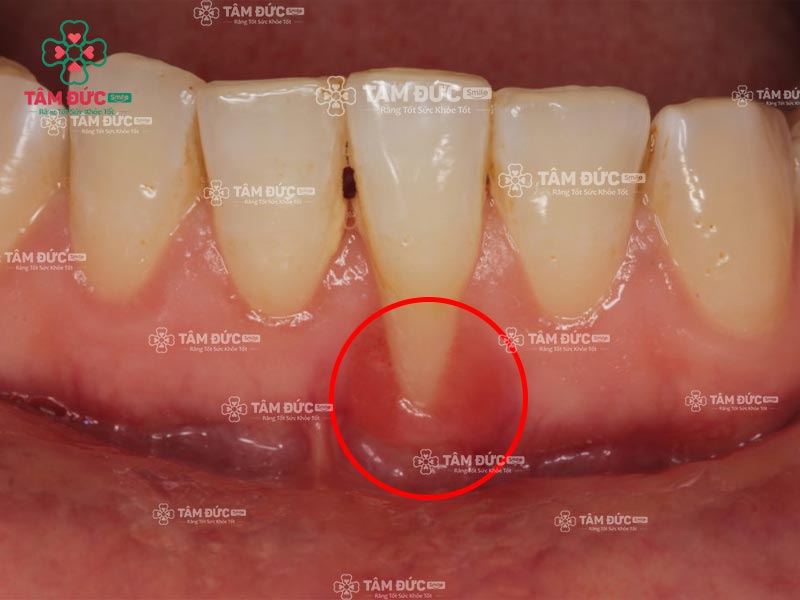

2.2. Giai đoạn viêm nướu chân răng nặng

Viêm nướu chân răng ở giai đoạn này sẽ gây rất nhiều phiền toái cho Quý khách vì ổ viêm đã xâm nhập vào ổ răng gây nên tình trạng:

- Nướu sưng đỏ, chảy máu và rỉ mủ.

- Nướu tụt, chân răng lộ rõ.

- Răng lung lay, dễ rụng.

- Cơn đau dữ dội kéo dài.

- Nướu có ổ mủ, áp xe.